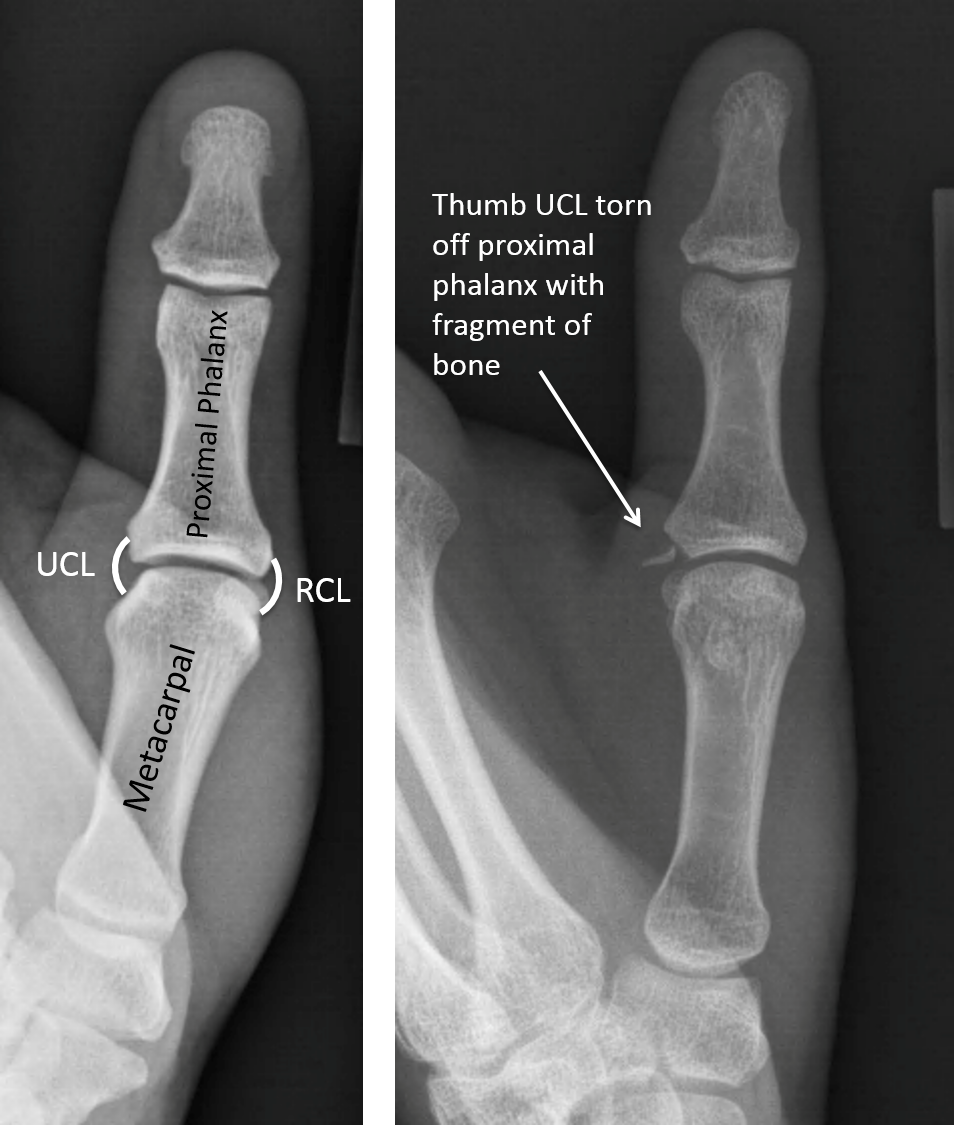

GAMEKEEPER'S THUMB (UCL TEAR)